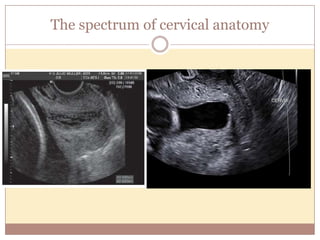

The spectrum of cervical anatomy

The spectrum ofcervical anatomy